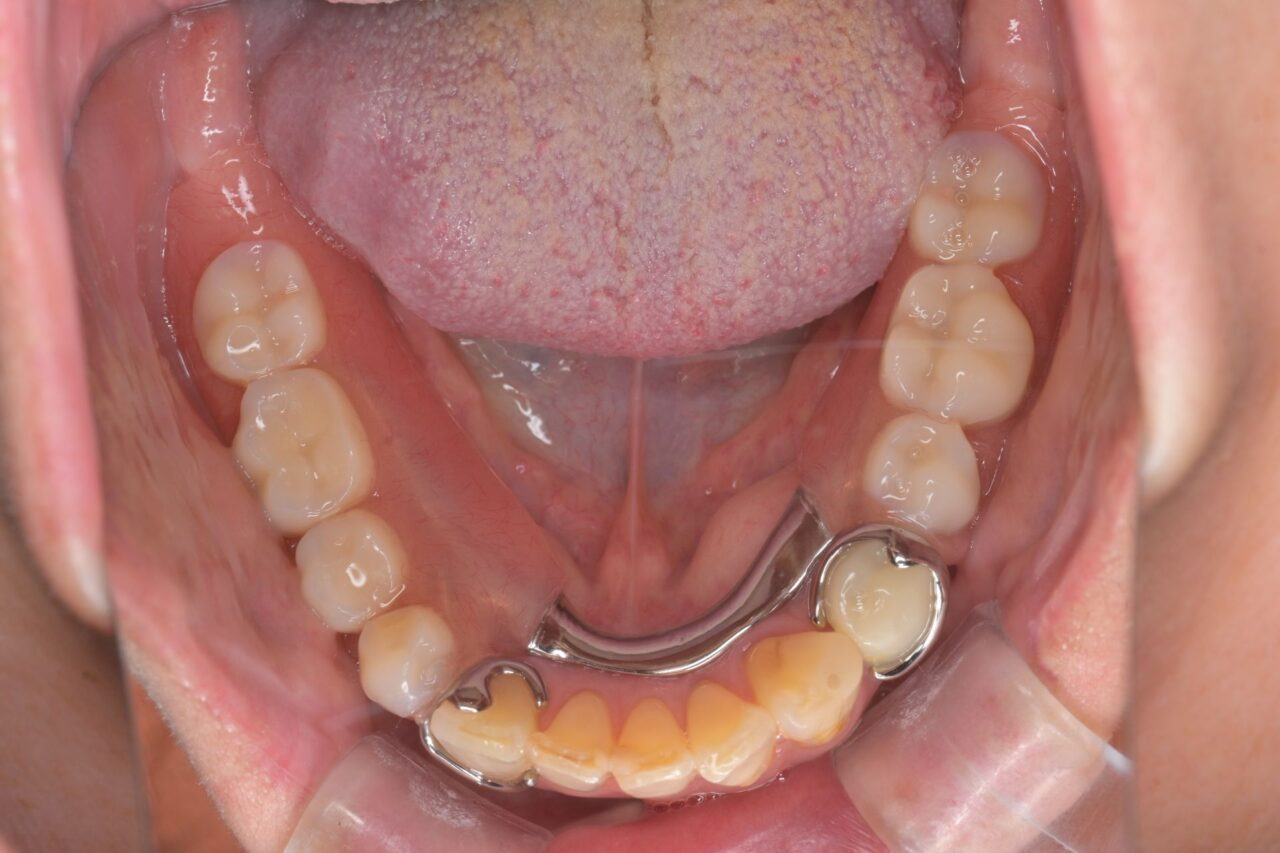

下面

奥歯は抜いて歯磨きがしやすい状況にしました。